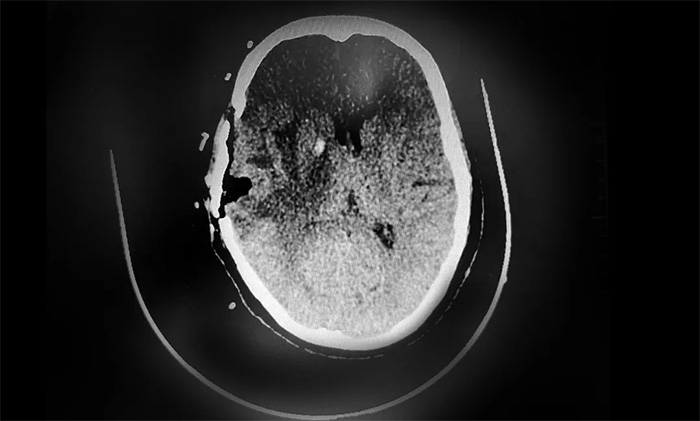

▲ CT复查示,肿瘤已被切除